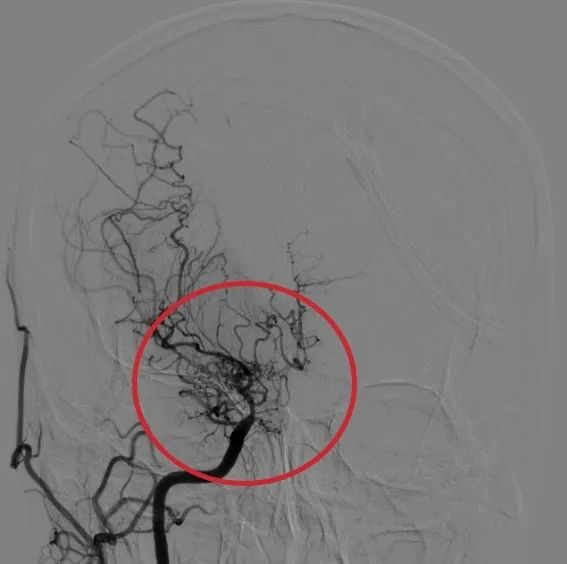

烟雾病(moyamoya disease,MMD)是一种以双侧颈内动脉末端及大脑前动脉、大脑中动脉起始部慢性进行性狭窄或闭塞为特征,并继发颅底异常血管网形成的一种脑血管疾病。Moyamoya这个词在日语中的意思是“一缕烟”。这种颅底异常血管网在脑血管造影(DSA)图像上形似“烟雾”,故称为“烟雾病”。烟雾病被认为是缺血性和出血性卒中的主要病因之一。

烟雾状血管 正常脑血管